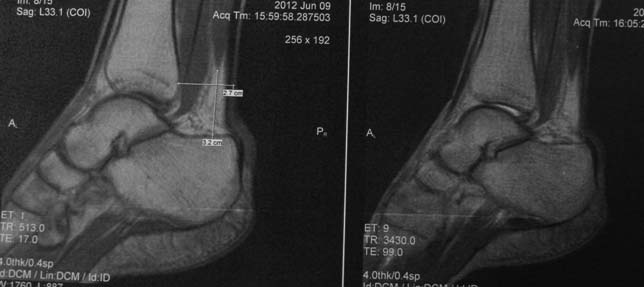

Уважаемые коллеги!

Спасибо всем, кто принимает участие в обсуждении случая. Досылаю рентгенограммы и МРТ. Хотелось-бы уточнить объем резекции пяточных костей.

Юрий Алексеевич Булахтин

Камчатский Военно-морской госпиталь